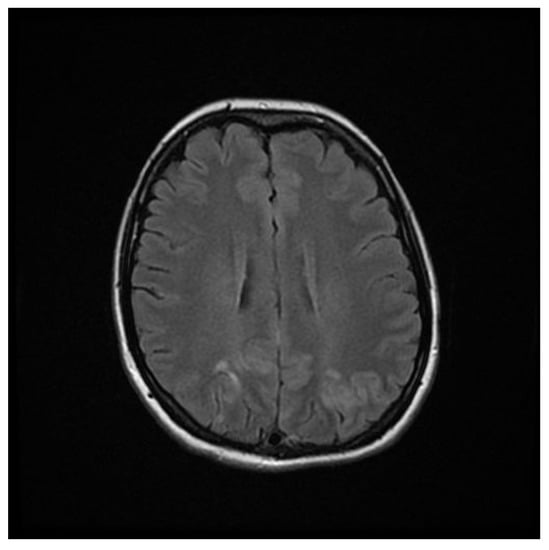

Computed tomography (CT) angiography of the head and CT with contrast were performed and excluded aneurysm, arteriovenous malformation (AVM), dural sinus thrombosis, and tumor. Due to the lack of deviations in the previous tests, an MRI of the head with contrast was performed, in which small areas and hyperintense bands in the T2-weighted image (T2-WI) and Fluid Attenuated Inversion Recovery (FLAIR) were visualized on both sides in the parieto-occipital areas without either diffusion restrictions or contrast enhancement, a typical manifestation of PRES [4], as shown in Figure 1, Figure 2, Figure 3 and Figure 4.

Figure 1. FLAIR MRI sequence of the brain showing hyperintense bands in the parieto-occipital areas on both sides.